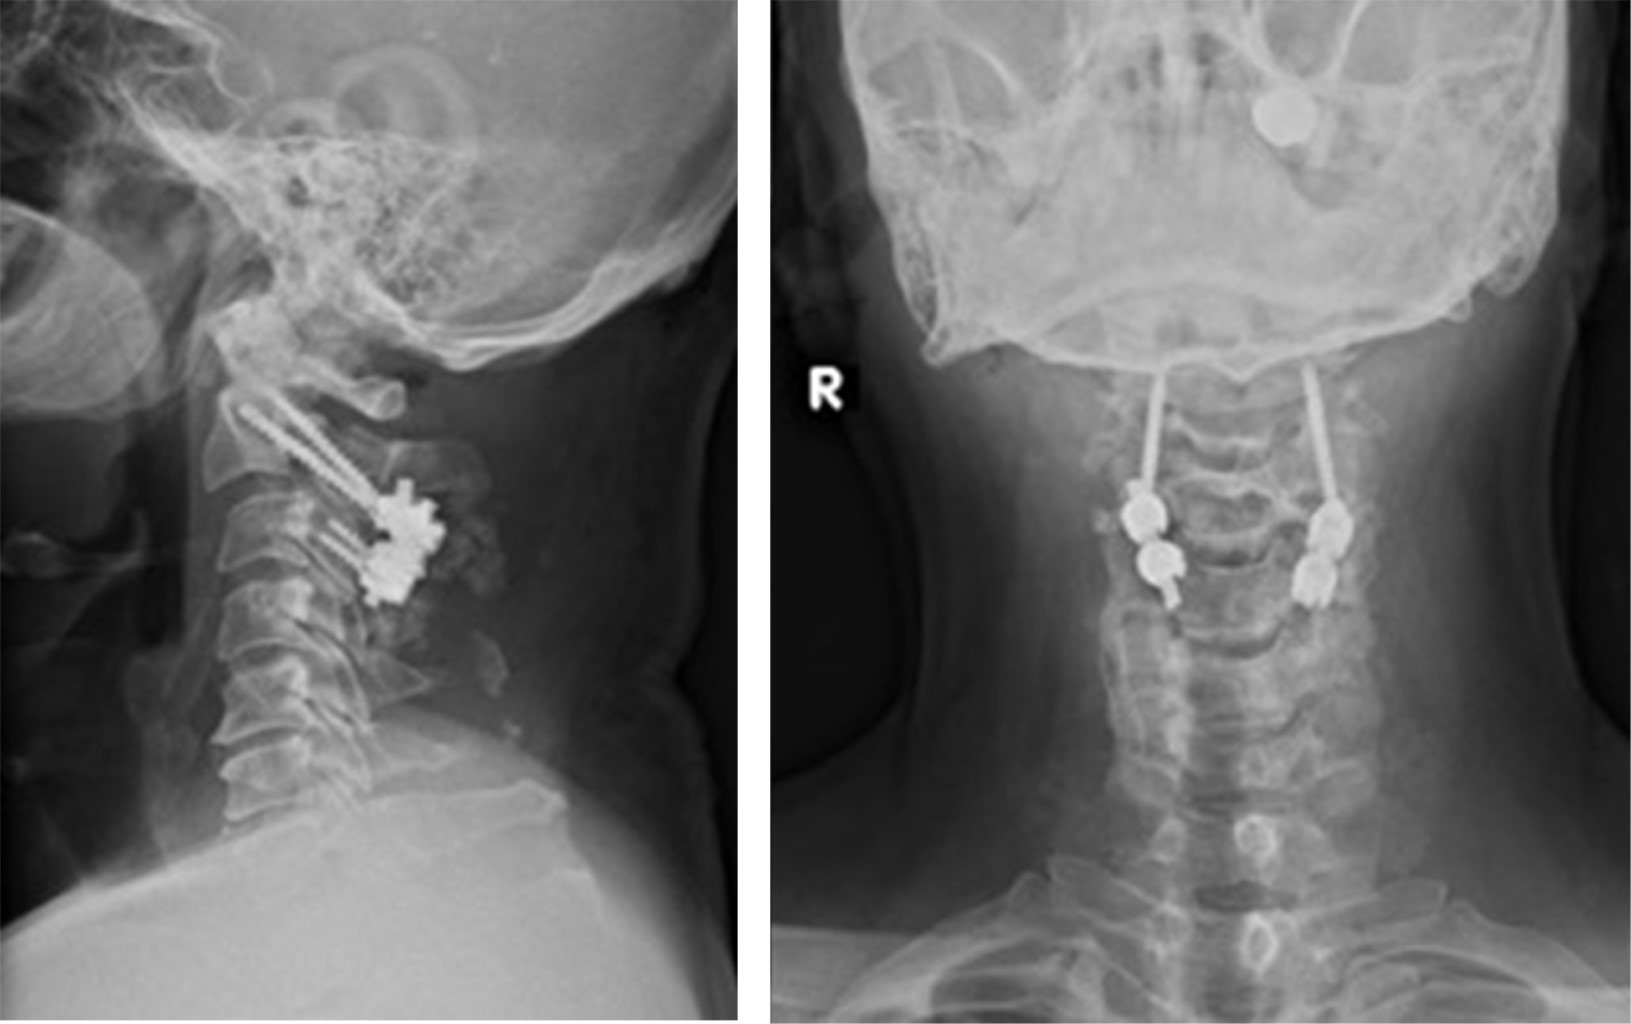

Fijación con tornillo transpedicular en C2 en el tratamiento de fractura de Hangman tipo III de Levine-Edwards: una opción para preservar el movimiento

Introducción: la fractura bilateral de la pars interarticularis de C2 por espondilolistesis traumática representa 4 a 7% de las fracturas cervicales y 20 a 22% de las fracturas de C2. La elección del abordaje quirúrgico sigue siendo controvertida; las opciones disponibles incluyen ACDF C2-C3, fusión posterior C2-C3, tornillo transpedicular de C2 solo y abordaje 360°. Presentación del caso: masculino, 60 años de edad, tras accidente automovilístico tipo volcadura, cursa con cervicalgia EVA 10/10, radiculopatía en C2-C5 derecha, fuerza 3/5 en escala MRC en C4-C5 derecho, reflejo bicipital derecho 1/+. TC con fractura de Hangman tipo III. Hicimos reducción cervical externa con apoyo de cabezal de Mayfield, abordaje cervical posterior y fijación trasnpedicular de C2, tornillos transmacizo facetario en C3 y barras laterales de titanio. Conclusions: las fracturas de Hangman tipo III deben diagnosticarse oportunamente debido al riesgo de lesión neurológica. Estas deben tratarse con fijación, si es posible con tornillo transpedicular en C2, que es una excelente opción para la reducción y estabilización de la fractura, mantenimiento de la alineación cervical y preservación de los rangos de movimiento.

Figura 1

Figura 2

Figura 3